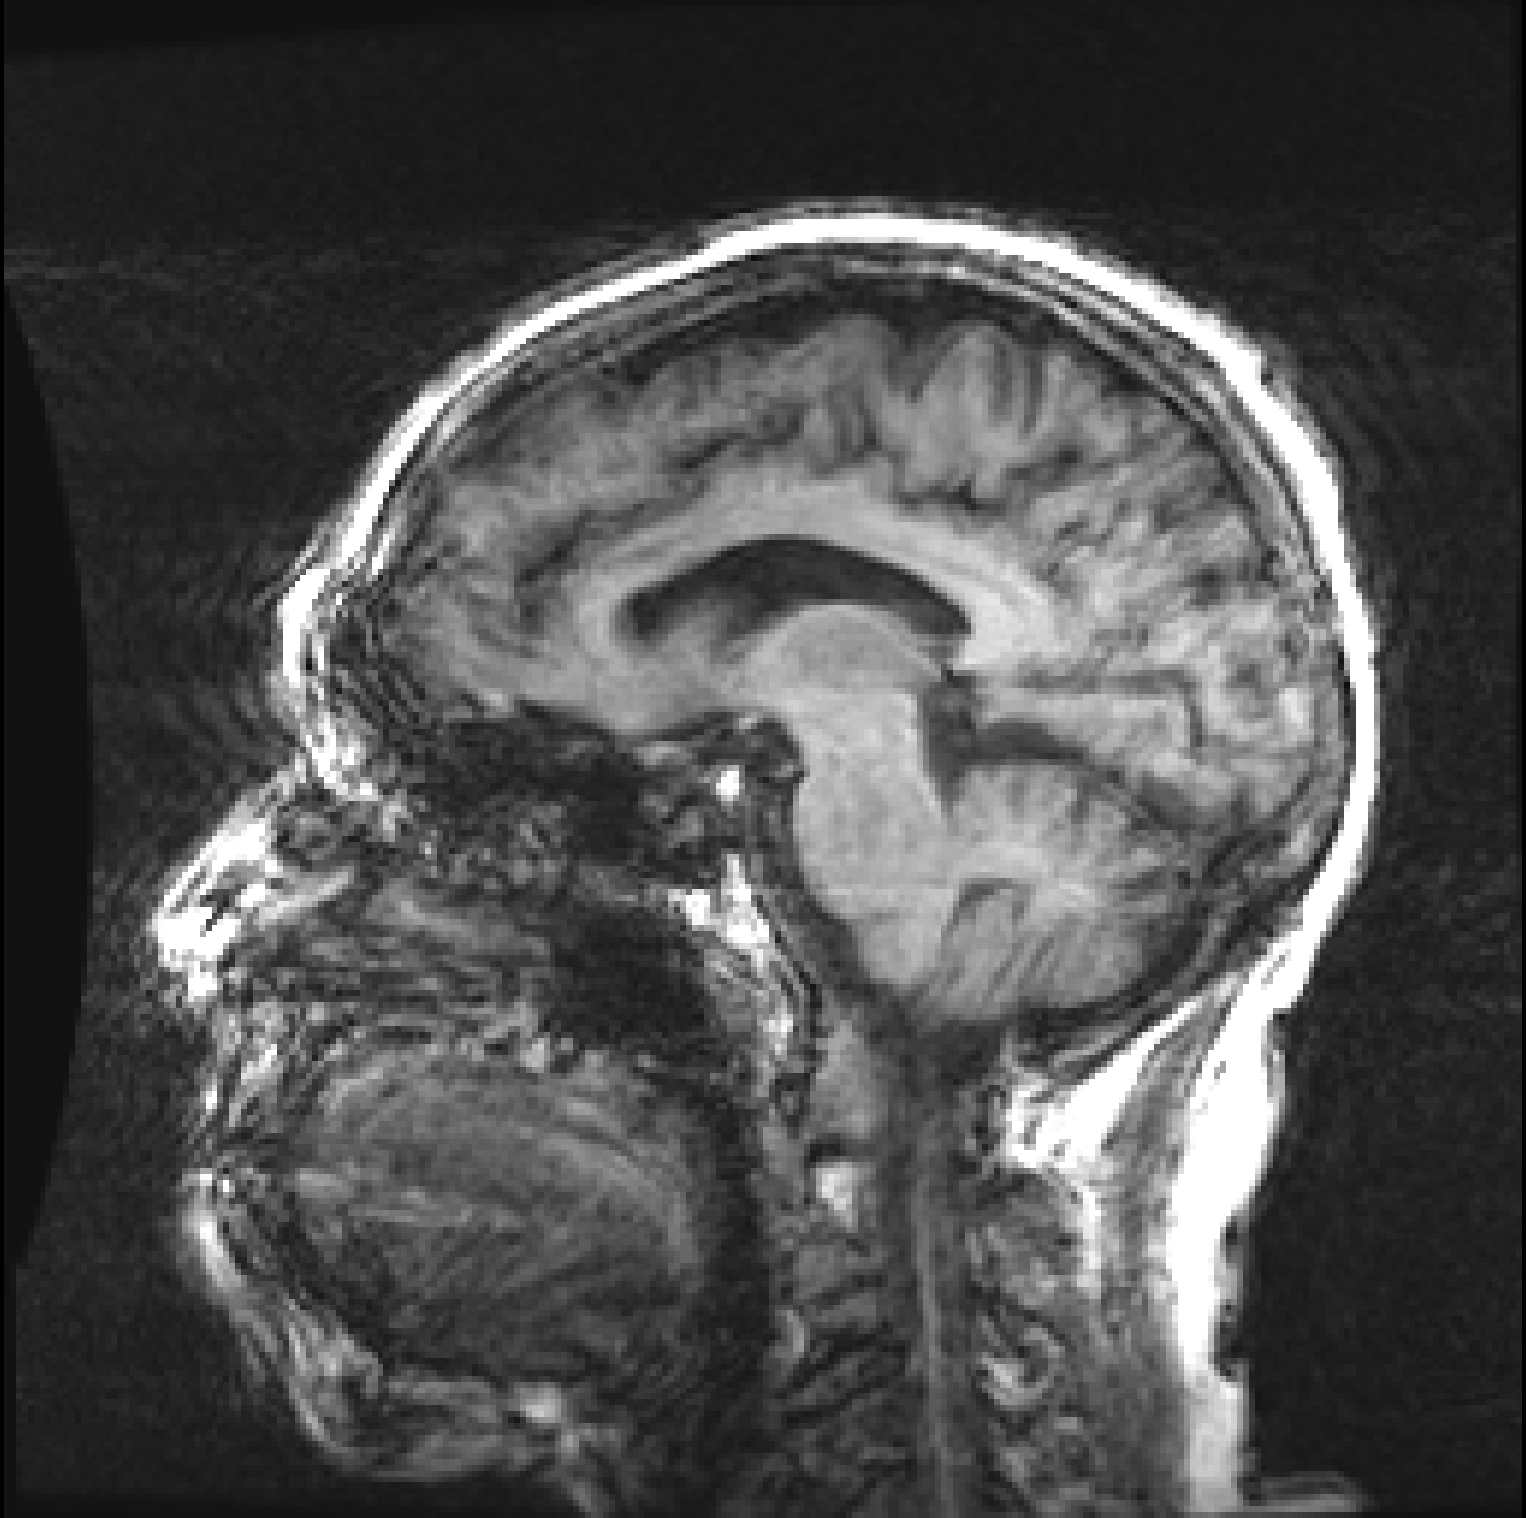

![]() |

| (a) | (b) |

Figure 1, presents two T1 images from the ADNI (Alzheimer’s Disease Neuroimaging Initiative) database, illustrating this difference. Both images, graded by trained analysts, have been deemed “unusable” for containing artefacts due to motion (the criteria used for the QC is described in detail on the ADNI website111http://adni.loni.usc.edu/methods/mri-tool/mri-analysis/). However, since in the right image the artefacts do not intersect the brain, the task of segmenting gray matter would not be affected and the scan should have been kept for this analysis. Thus, there is a distinction between perceptual quality and the quality required for algorithmic processing. Furthermore, by training with augmentation, convolutional neural networks (CNNs) make the internal representation of the data more robust to noise, so from an algorithmic perspective, some image degradation may be tolerated before observing a drop in performance. These observations allow us to define MRI quality as the model’s ability to perform the task, rather than a subjective visual grading of quality.